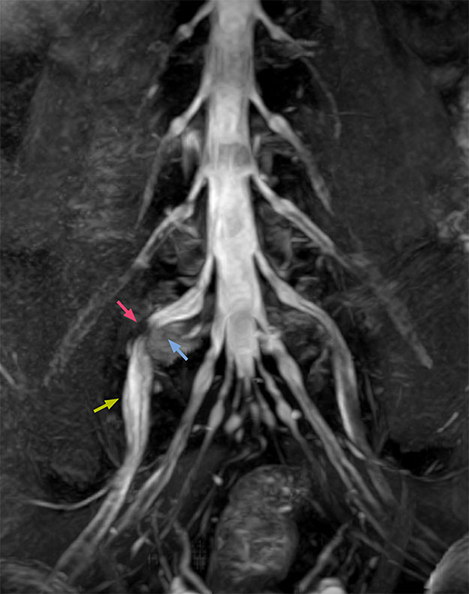

“In such case, we would then browse through axial T2-weighted MR images slice by slice and mentally reconstruct the actual situation based on both radiculography and MRI. Fortunately, NerveVIEW can now very well show nerve courses and presence of nerve compression or edema in one single image series.” “We have often seen NerveVIEW directly depict details of the nerve compression that were not observed by radiculography. Therefore, we think that with NerveVIEW we can reduce the number of invasive examinations, especially for some patients with lumbar plexus symptoms.”

“The intra-luminal signal of veins, especially around the intervertebral space, can be suppressed well with NerveVIEW. As a result, we can easily observe the detailed nerve structure around the posterior ganglion,” he says. “This is why we use 3D NerveVIEW for intraforaminal stenosis and extraforaminal stenosis/herniation (lateral disc herniation). On the other hand, if herniation is suspected to exist inside the dorsal root ganglion (DRG), balanced TFE or ProSet-FFE is applied. NerveVIEW is not suitable for evaluating the median type of herniation.” The SE-EPI DWI-based method for MR neurography works well for large FOV exams like whole-body MRI, but focal examination of nerves is often limited by the attainable spatial resolution (both inplane and slice direction) and geometric distortion. “3D NerveVIEW achieves higher in-plane resolution – close to our other routine spine sequences – and the source images can be used instead of adding a fat-suppressed T2-weighted sequence,” Tanji says.

According to Tanji, methods such as ProSet FFE, STIR or 3D VISTA are anatomically nonselective because background signals, for instance from blood vessels, often interfere with nerves, which hampers evaluation of details, especially at the peripheral side of the nerves.

“NerveVIEW can clearly show nerve courses and presence of nerve compression. However, when multiple abnormalities are seen, it can still be hard to determine which nerve is causing the symptoms,” says Dr. Yabuki. “In our experience so far, we see abnormal findings on NerveVIEW in about 70% of elderly patients. As the pain is usually caused by only one nerve, we thus need to find the exact corresponding nerve.” “With a nerve root block, the patient's pain is improved by infiltration of local anesthesia directly around the nerve root considered to be responsible. Knowing such nerve root block findings prior to image interpretation, helps to easily recognize abnormal findings on NerveVIEW as well. In other words, without a priori knowledge, based on symptoms and/or nerve root block findings, we must be aware of the possibility of overdiagnosis.”